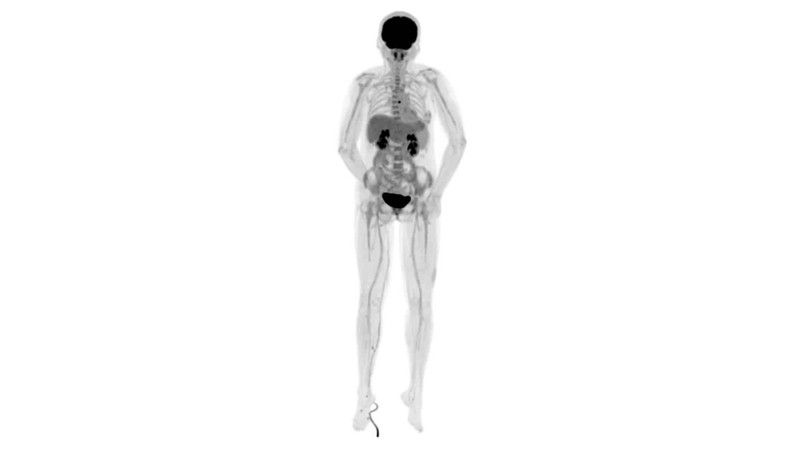

肺癌轉(zhuǎn)移及復(fù)發(fā)

患者男性,66歲,七年前發(fā)現(xiàn)右肺肺癌,其間手術(shù)兩次,共切除兩個肺葉,復(fù)查;

診斷意見,回腸轉(zhuǎn)移,右肺殘留部復(fù)發(fā)